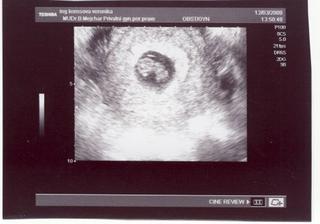

12.3. - první prohlídka v poradně a už jsme dostali těhotenskou průkazku!!! máme další fotečku, kde už miminko vypadá opravdu jako človíček 🙂)